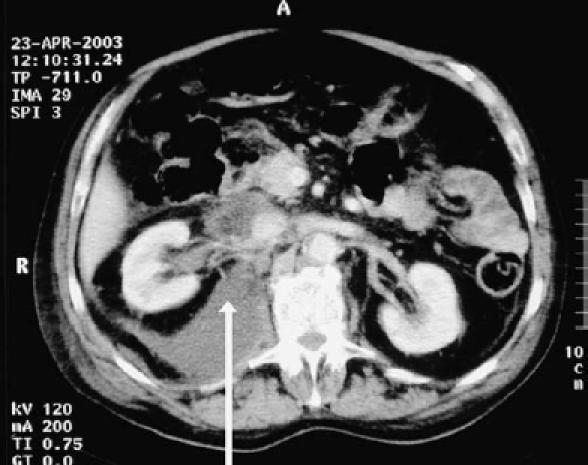

Biliscrotum and retroperitoneal biloma: spontaneous rupture of the biliary system presenting as an incarcerated inguinal hernia.

Spontaneous rupture of the biliary system is a well documented condition in infants but is rare in adults. We report the case of a 73-year-old gentleman who presented with clinical signs and symptoms mimicking that of a strangulated right inguinal hernia. At emergency operation the scrotum was found to contain bile. Following radiological imaging and exploratory surgery, a large retroperitoneal biloma was found. We discuss the clinical signs associated with biliscrotum and retroperitoneal biloma and describe our operative management of this patient. We review the previously reported cases of these rare clinical entities. We found that our case exhibited similarities in terms of the age of presentation and presence of distal common bile duct stones. This is, to our knowledge, the only reported case of a patient presenting with biliscrotum secondary to the assumed spontaneous rupture of the common bile duct and development of a retroperitoneal biloma.